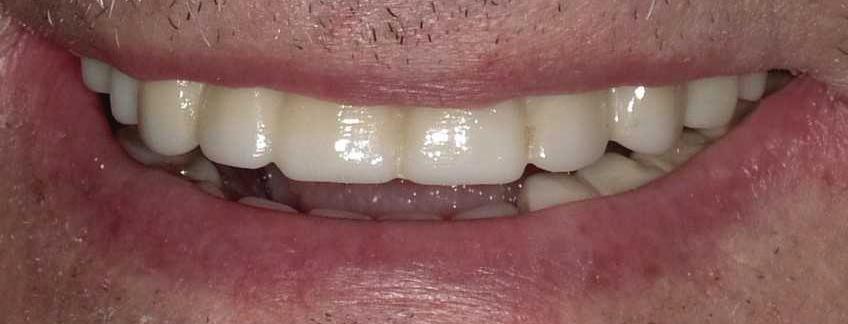

Submitted By Sivakumar Sreenivasan, DMD, MDS Dental Implant Center of Rockville

Tooth loss is extremely common among adults, especially as we age. Rather than living with the discomfort and hassles of dentures, many people are opting for what is called “all-onfour” dental implant restoration.

An implant is a small titanium

screw that fits inside your jawbone and replaces the root-part of a missing tooth. Minor surgery is required to insert the implants. Once the implant is in place, a crown is attached to give you a highly realistic-looking and functional prosthetic tooth.

You do not need a dental implant for each and every one of your missing teeth. All you need is four precisely placed implants on the top of your mouth, and four on the bottom, to restore your full smile. That’s the beauty of the all-on-four. And because the implant is made of titanium, it has the unique ability to fuse to living bone and function as part of it. So eventually, the dental implant becomes part of the jawbone and serves as a strong, longlasting foundation for your new teeth.

Besides ensuring that your implants are permanently fixed in place, this bone fusion has another important benefit: it prevents future bone loss in the jaw. This helps to maintain a more youthful facial structure – and better